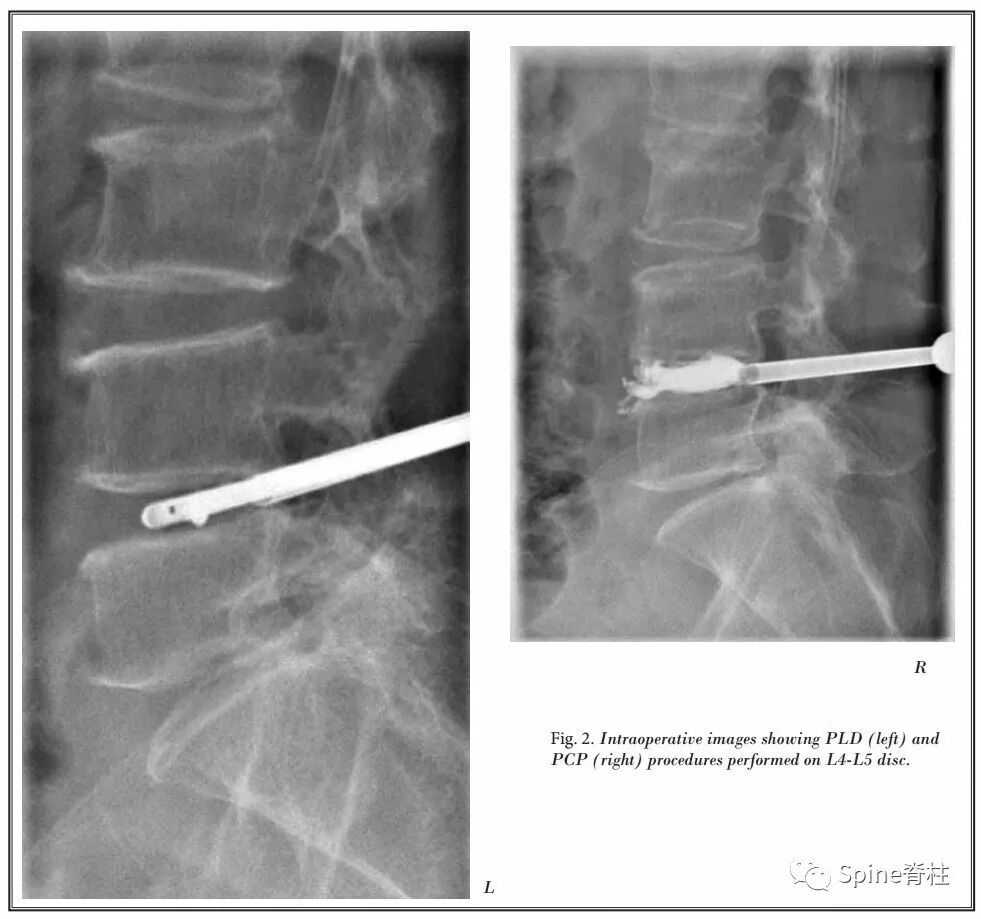

PCD与经皮腰椎间盘切除术(PLD)相结合

-

2017年,一篇来自中国(上海交通大学附属第六医院放射科)的研究,将PCD与经皮腰椎间盘切除术(percutaneous lumbar discectomy,PLD)相结合治疗症状性腰椎间盘突出症伴随终板Modic I型改变患者,取得了较好的效果。

此研究,评估了PLD+PCP治疗7例症状性腰椎间盘突出症伴随终板Modic I型改变患者,术后VAS和ODI评分明显改善,且无明显并发症的发生。

典型病例

最后作者总结,PLD+PCP可作为老年腰椎间盘突出症和Modic I型终板改变患者的可选治疗方法,对介入放射科医生来说是非常可行的。

对于因一般情况不佳难以耐受传统开放手术或不愿意接受开放手术的患者来说,这似乎是一个很有希望的选择。

此外,这是一种微创技术,可在清醒镇静下进行,并发症发生率极低,住院时间短。

同时,作者也指出需要进一步研究,更大的样本量,并与其他可用的治疗方法进行比较,以明确这些初步结果。